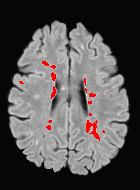

Patch size is another important parameter of the network. In computer vision applications such as object detection, usually a whole 2D image is used as a feature. However, full 3D medical images can not typically be used because of memory limitations. Fig. 4 shows examples of lesion memberships obtained with different sized 2D patches. As the patch sizes increases, the false positives that are mostly observed in the cortex tend to decrease. Fig. 5 shows a plot of Dice and LFPR with various patch sizes, ordered from left to right according to their increasing size. Note that smaller patches ( to ) produced significantly lower Dice and higher LFPR compared to other patches (), as seen from the memberships in Fig. 4. Also some of the highest Dice and lowest LFPR were observed for patches with large in-plane size, i.e., , , and . It was observed in Fig. 5 that there is no significant difference between Dice coefficients for , , or , but LFPR of both and are significantly lower than that of (). We chose as the optimal patch size. Other choices of smaller and patches (not shown) yielded worse results. Note that although training was performed with different patch sizes, the memberships were generated slice by slice, as the trained model consisted only of convolutions and did not need any information about patch sizes.

In our experiments, we used large 2D patches similar to Ghafoorian et al. (2017b), in comparison to isotropic 3D patches as used before, e.g., in Valverde et al. (2017), in Wachinger et al. (2017), and in Kamnitsas et al. (2017). The rationale behind using large anisotropic patches is twofold. First, experiments with full 3D isotropic or patches showed little or no improvement in Dice and led to increased false positives, with memberships similar to the one with patches, as shown in Fig. 4. Larger isotropic patches, e.g. or , showed inferior segmentation, and in some cases, optimization did not converge. The reason is that the FLAIR images in the test datasets had inherently low resolution in the inferior-superior direction, mm and mm compared to in-plane resolution of mm. Therefore 2D axial patches capture the high resolution in-plane information that represents the original thick axial slices. Second, the lesions are usually focal and small in size, unlike other brain structures. Therefore a very large isotropic patch around a small lesion can include superfluous information about the lesion, which can increase the amount of false positives. Note that with in more recent studies employing high resolution 3D FLAIR sequences, it is trivial to extend the algorithm to accommodate for 3D patches.